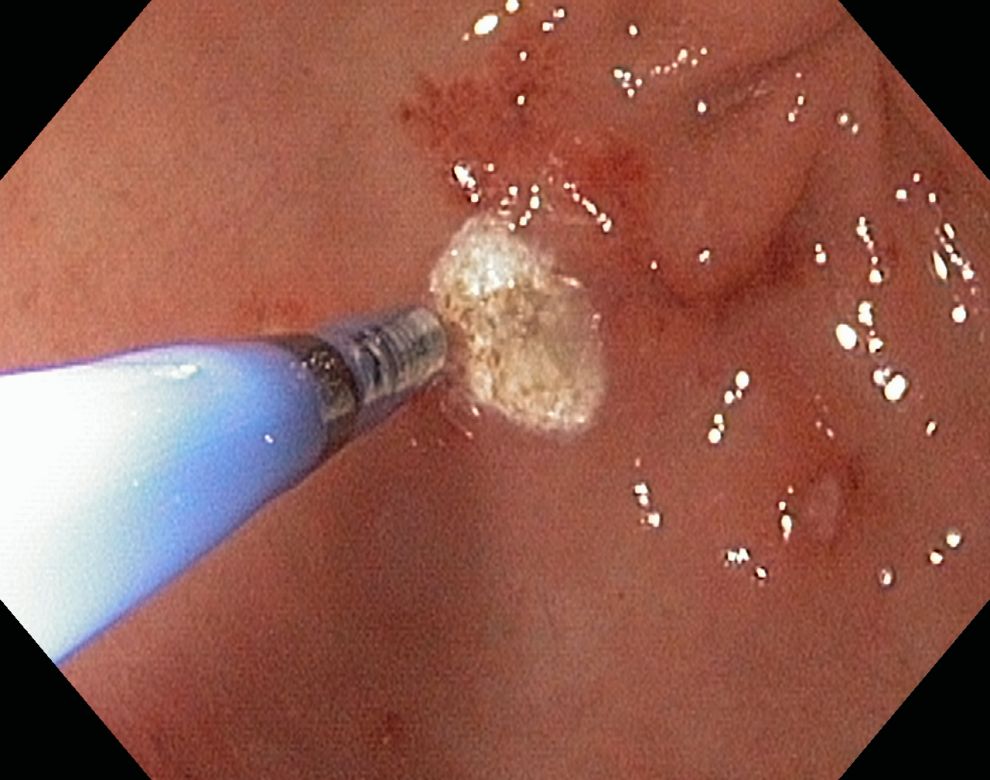

Was leistet der Argon-Beamer?

Bei endoskopischen Untersuchungen leistet auch der Argon-Beamer wertvolle Dienste. Kontaktlos bringt er Hochfrequenzstrom auf die innere Oberfläche im Magen, Dünndarm oder Dickdarm auf. Dabei kommt es zur Verkochung des Gewebes, so dass Blutungen, mögliche Blutungsquellen (z. B. Gefäßmissbildungen, sog. Angiodysplasien) wie auch Tumore behandelt werden können.